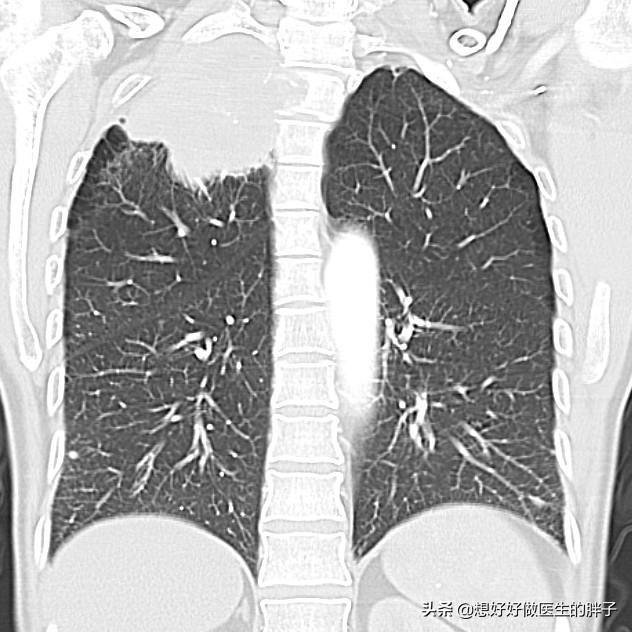

●Maladies pulmonaires.. Il est relativement rare qu'une maladie pulmonaire soit à l'origine de douleurs à l'épaule et au dos, mais il existe un type de cancer du poumon appelé "cancer de l'épaule".cancer du poumon apicalCette tumeur n'induit pas de symptômes spécifiques dans les premiers temps, mais au fur et à mesure qu'elle se développe, elle envahit lentement la plèvre et peut provoquer des douleurs à l'arrière de l'épaule.

En cas de suspicion, il est important d'effectuerTomodensitométrie des poumonsIl s'agit de préciser s'il existe un espace réservé.

Il peut également y avoir des problèmes relativement rares, tels que des maladies pulmonaires qui peuvent causer des douleurs à l'endroit concerné, et principalement dans la partie supérieure droite du poumon, comme les tumeurs pulmonaires, qui ne peuvent pas être complètement exclues et qui doivent être examinées à temps pour confirmer le diagnostic.